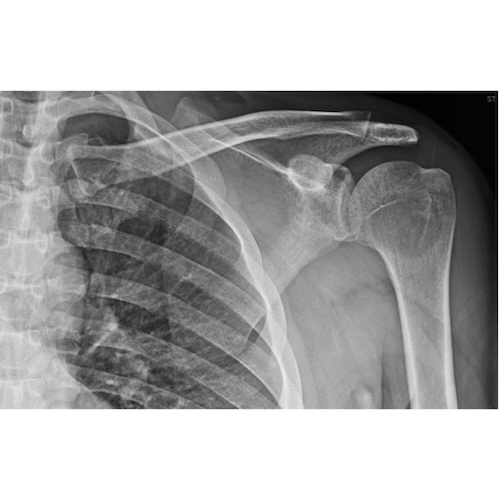

| Lurking In The Acoustic Shadows: Uncovering An Uncommon Diagnosis With Ultrasound - Page #3 | |||